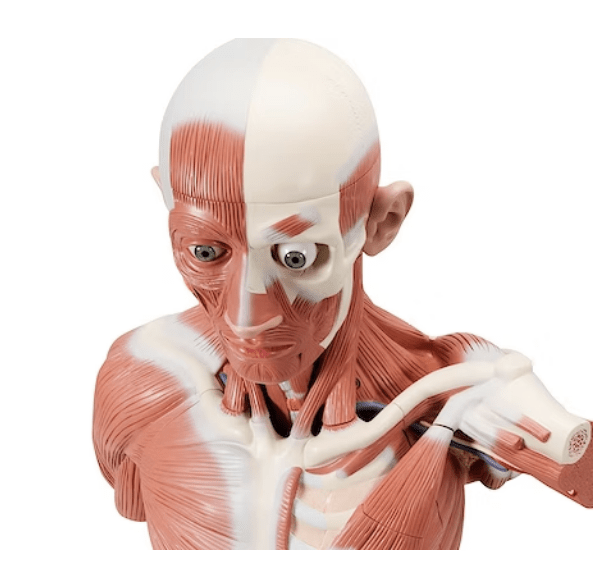

Anatomisk modell av det sympatiska nervsystemet

Anatomisk modell som illustrerar det sympatiska nervsystemet, sett i relief från höger sida av kroppen. Modellen är särskilt detaljerad kring plexus cardiacus och plexus sacralis.

Modellen väger 4,3 kg och följande mått

- Längd: 10 cm

- Bredd: 25,5 cm

- Höjd: 74 cm

Modellen levereras fast monterad på grönt underlag